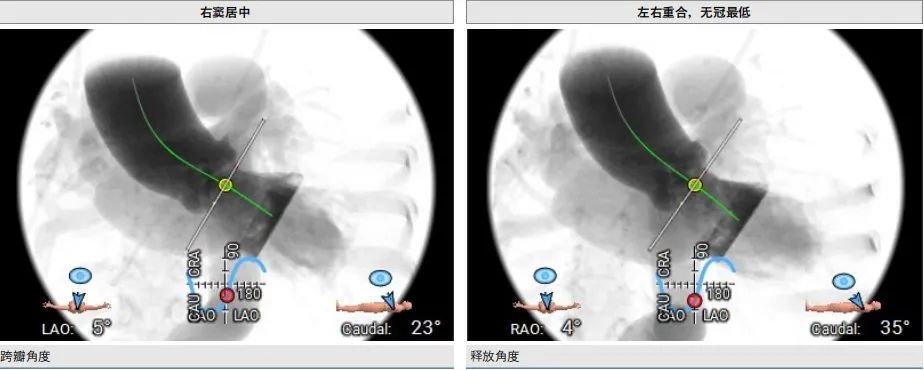

手术策略分析

♦ 患者主动脉瓣环水平角度63°(横位心),器械过弓跨瓣会存在一定的困难,计划提前预埋Snare辅助

♦ 释放:左右重合位,瓣环下0位释放,再结合正交体位进一步评估瓣膜植入深度

右窦居中,无窦最低